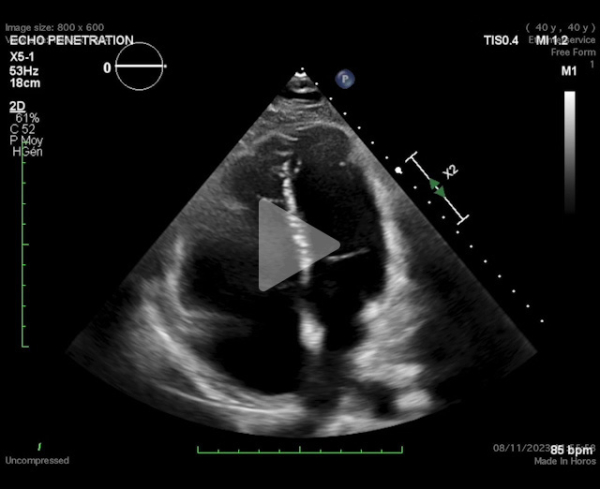

Imagerie : échographie transthoracique et scanner thoracique

(Vidéo 1, Figures 2 et 3)

- FEVG 60%, dilatation VD sévère, PAPs=65mmHg

- Paramètres VD : TAPSE=11 - Onde S=8 - Diamètre anneau=42mm - Strain VD=-11,9%

Vidéo 1 : échographie transthoracique

Figure 2 : ETT - Strain VD